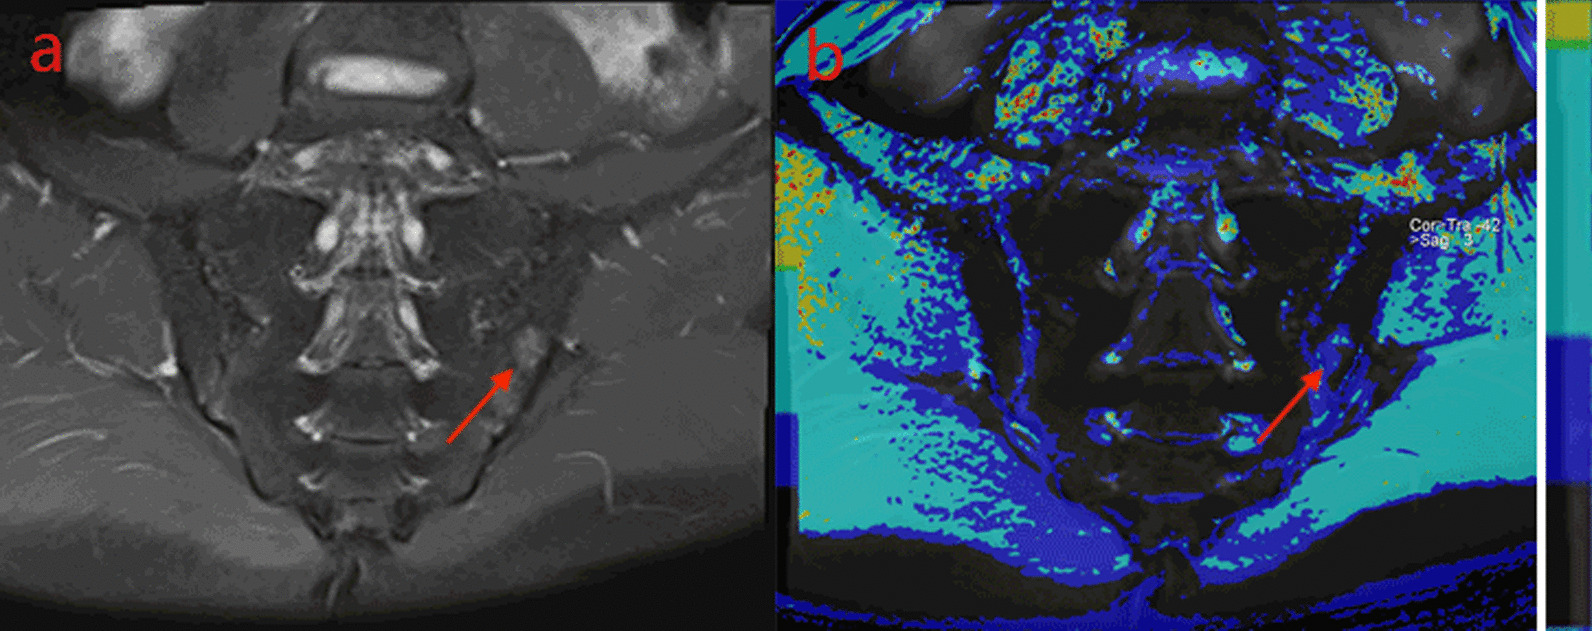

Fig. 3.

A male, 24 years old, HLA-B27: ± , ASDAS-CRP:3.8, belongs to the very high disease activity group. Depending on the different treatment cycles, these are pre-treatment (A,a), 3 weeks (B,b), 6 weeks (C,c) and 12 weeks (D,d) after treatment, respectively. A–D. Fat suppression PDWI sequences show the decreasing of sacroiliac bone marrow signal, gradually. the ASDAS-CRP score decreased with the increase of the treatment cycle (2.6, 1.6, 1.0, 0.6). a–d. T1-mapping pseudo-color diagrams also demonstrate the decreasing of the regions of interest T1-mapping value, gradually. (956.43, 780.73, 604.73, 349.27 ms).

Comparison of relaxation time of subchondral bone marrow water content among three subgroups in the Activity group

Different relaxation time values of sacroiliac joints appeared in moderate activity group, high disease activity group, and very high disease activity group (Table 5). Values of T1 mapping (Fig. 1b, 2b, 3a), T2* mapping and T2 mapping in each subgroup of the Active group increased with the increase of disease activity, and the color deepened on the pseudo-color map. Using Kruskal–Wallis H test, the difference of T1 mapping value among each group was statistically significant. (iliac H = 11.496, P = 0.003; sacral H = 11.954, P = 0.003). After the pairwise comparison of correcting the significance level by Bonferroni method, it was found that there were significant differences in T1 mapping between moderate group and very high disease activity group (iliac P = 0.002, sacral P = 0.004) and between high disease activity group and very high disease activity group (sacral P = 0.018, iliac P = 0.029). However, there was no significant difference between moderate activity group and high disease activity group (iliac P = 0.494, sacral P = 0.878,). There was no significant difference in values of T2 mapping and T2* mapping in the subgroup of the active group (iliac P = 0.455, sacral P = 0.703), (iliac P = 0.191, sacral P = 0.457).